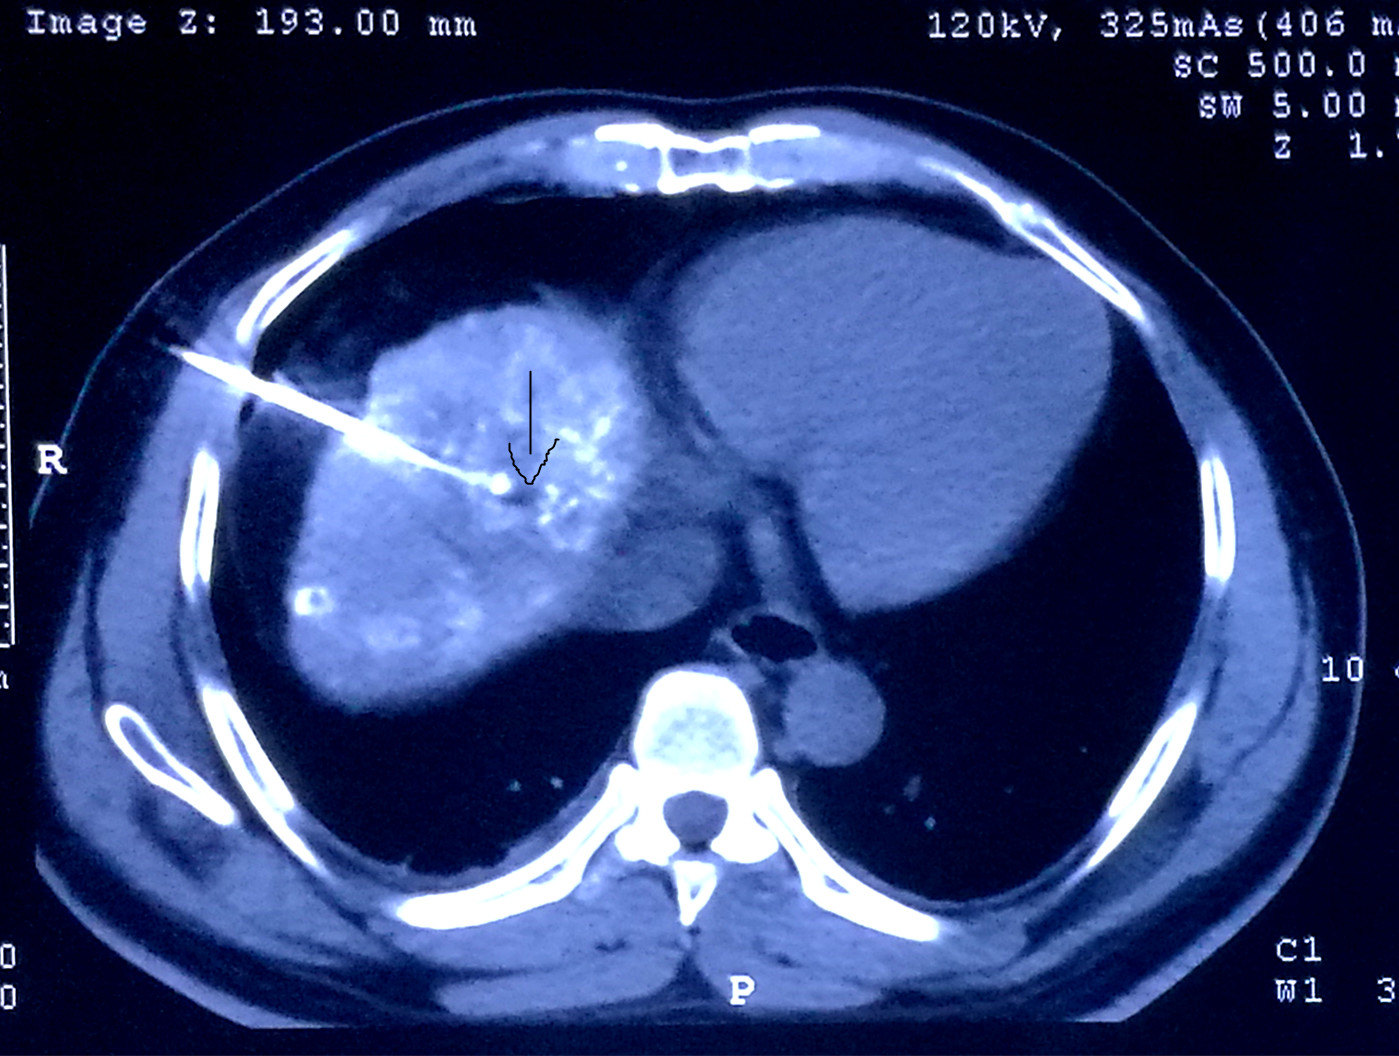

术前必须搞明白,立马做DSA,果真发现另外两个微小病灶,一个在8段,一个在5段,随即做了TACE,将三个病灶全部栓塞。一周后在CT引导下我用射频将三个病灶全部毁损,效果很不错。